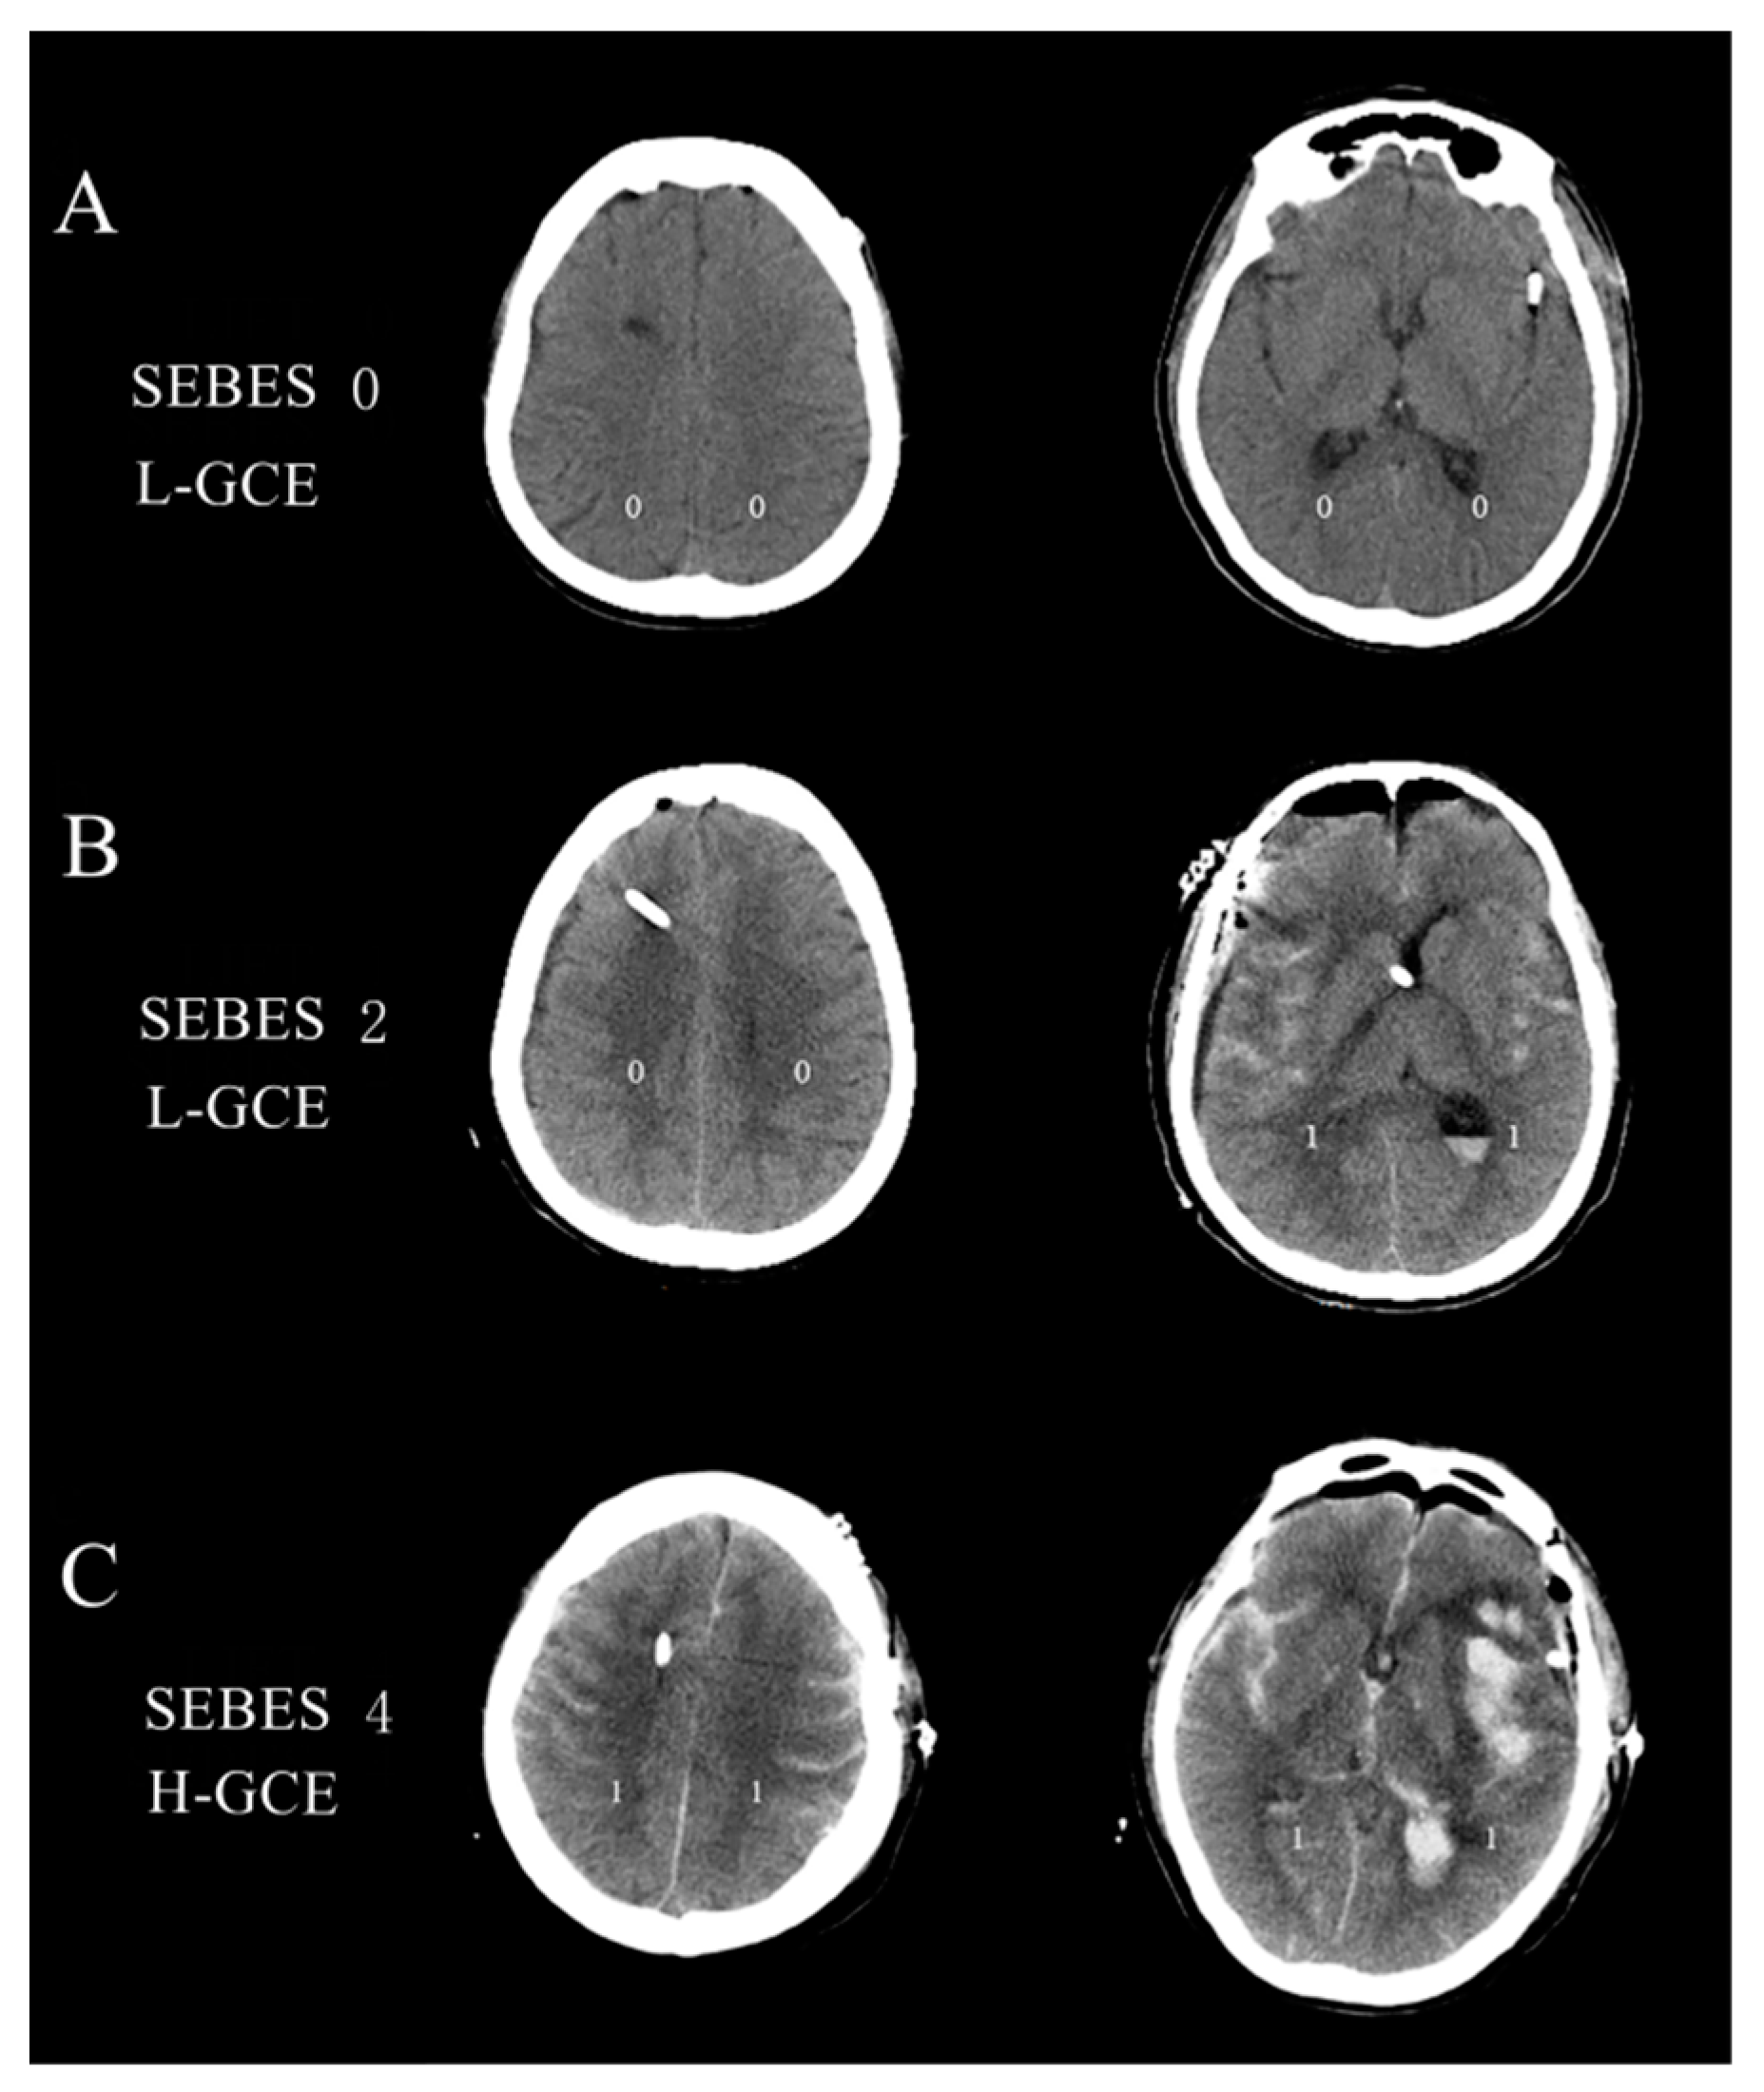

2.4. Clinical Outcome Assessment

- Ahn, S.H.; Savarraj, J.P.; Pervez, M.; Jones, W.; Park, J.; Jeon, S.B.; Kwon, S.U.; Chang, T.R.; Lee, K.; Kim, D.H.; et al. The Subarachnoid Hemorrhage Early Brain Edema Score Predicts Delayed Cerebral Ischemia and Clinical Outcomes. Neurosurgery 2018, 83, 137–145. [Google Scholar] [CrossRef]

- Eibach, M.; Won, S.Y.; Bruder, M.; Keil, F.; Herrmann, E.; Berkefeld, J.; Seifert, V.; Konczalla, J. Age dependency and modification of the Subarachnoid Hemorrhage Early Brain Edema Score. J. Neurosurg. 2020, 134, 946–952. [Google Scholar] [CrossRef] [PubMed]